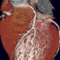

Υπάρχει ένας εναλλακτικός τρόπος για να πραγματοποιηθεί μια στεφανιογραφία, με τη χρήση αξονικής τομογραφίας θώρακα (CT). Η αξονική στεφανιογραφία δείχνει επίσης την ύπαρξη στενώσεων στις αρτηρίες που αιματώνουν την καρδιά, παρόμοια με μια παραδοσιακή στεφανιογραφία. Ωστόσο, σε αυτή τη μορφή στεφανιογραφίας, το ιωδιούχο σκιαγραφικό χορηγείται σε μία μικρή φλέβα στο χέρι του ασθενούς και όχι απευθείας στις στεφανιαίες αρτηρίες διαμέσου καθετήρων που εισάγονται σε αρτηρία. Αυτό καθιστά την εξέταση λιγότερο επεμβατική από μια παραδοσιακή αγγειογραφία, εξ ‘ου και η ευρέως χρησιμοποιούμενη ονομασία της ως «αναίμακτη στεφανιογραφία». Γενικά, η αξονική στεφανιογραφία δεν είναι εξίσου αποτελεσματική στην ανίχνευση στενώσεων σε μικρούς κλάδους των κύριων στεφανιαίων αρτηριών, σε διακλαδώσεις και προυπάρχοντα stent, ενώ η εξέταση δέν είναι εφικτή σε όλους τους ασθενείς (πχ ασθενείς με έντονες επασβεστώσεις των στεφανιαίων αγγείων η σημαντικές αρρυθμίες). Η κλασσική στεφανιογραφία εξακολουθεί να είναι ο καλύτερος τρόπος διάγνωσης της στεφανιαίας νόσου. Ο γιατρός σας θα συζητήσει μαζί σας τους ιδιαίτερους κινδύνους και τα οφέλη καθεμίας μεθόδου.